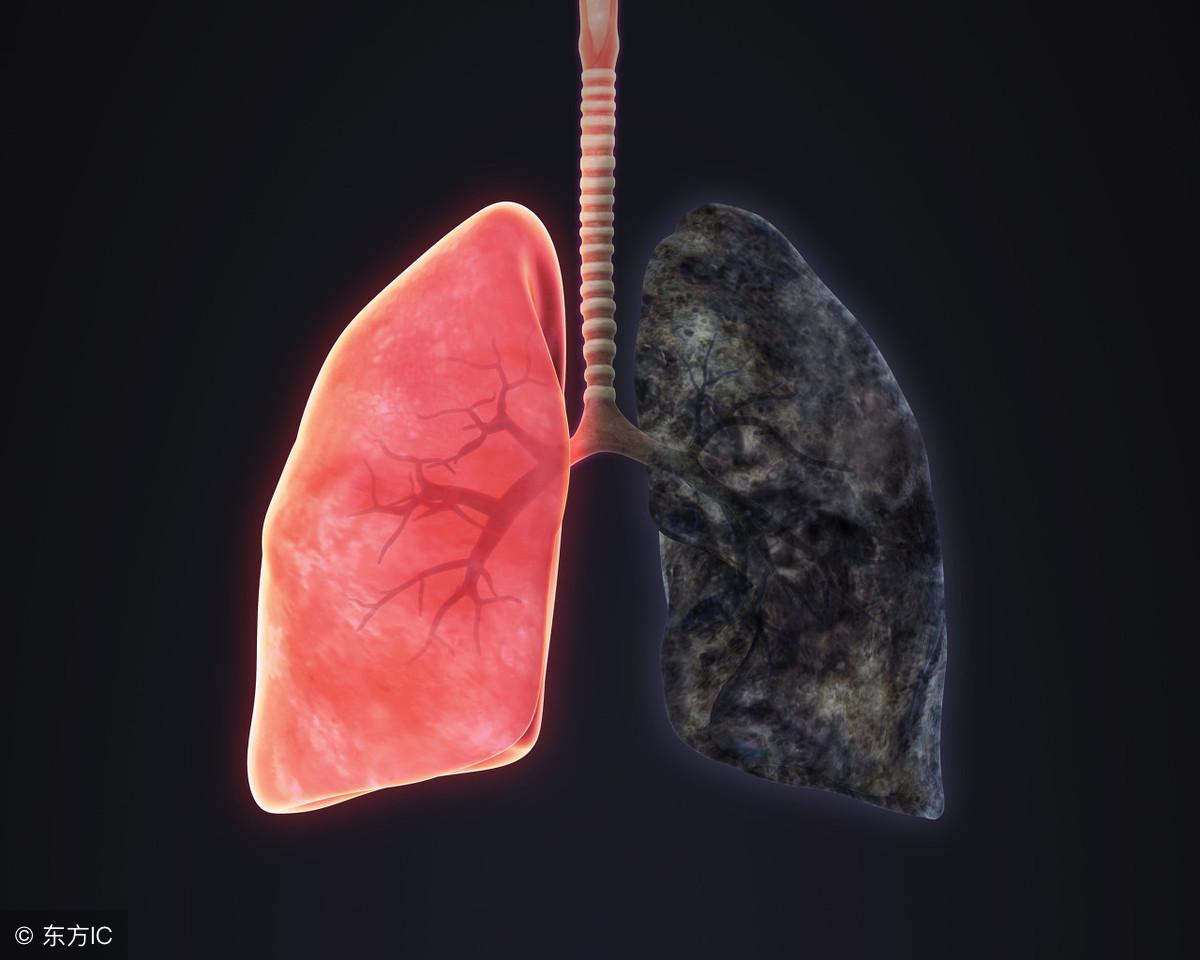

阻塞性肺气肿为支气管炎最常见的并发症,阻塞性肺气肿以呼吸困难为主要症状,并逐步导致肺部纤维化,造成不可逆损害,甚至诱发肺源性心脏病,给患者的生命带来威胁。

支气管炎反复发作,支气管粘膜充血,水肿,形成溃疡,管壁纤维增生,管腔或多或少变形,形成支气管扩张或狭窄。支气管扩张的症状以反复的咳嗽、咯血为主。

支气管炎反复发作,导致腺体增生肥大,分泌功能亢进等,形成不可逆转的病理改变,降低肺功能。防治不好的话不但会并发肺气肿还有可能发展为肺原性心脏病。所以不管我们平时有多忙,在工作之余都要重视我们的身体健康,身体不适要及时到医院就诊,及时治疗,只有这样我们的生命财产安全才能够得到保障。